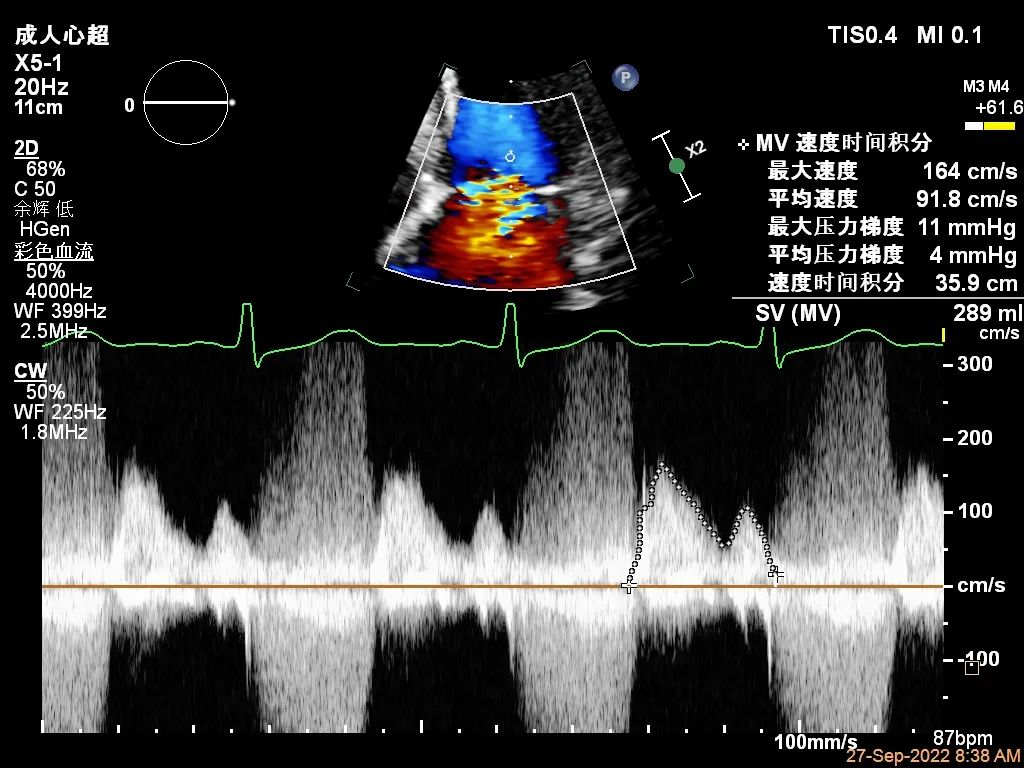

“贞”心一“课”|TEER成功治疗外交界隆起合并P3区宽大Flail病变一例